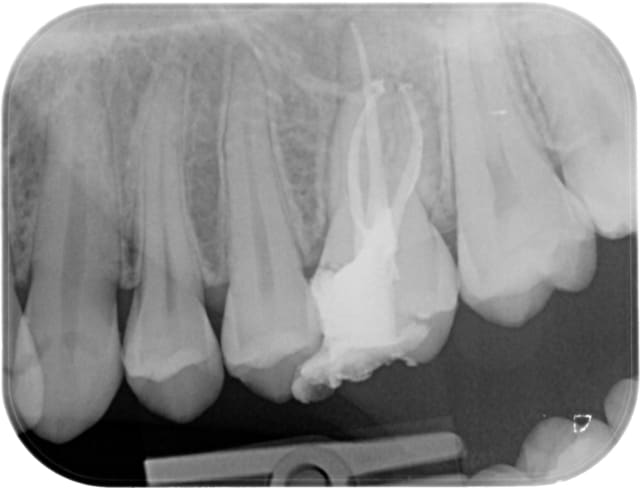

Ici avec de l'AlphaKite de chez Komet: lime 25 6% pour la 24 et Lime 25 6% puis finition 25 8% pour la 25.(moteur ATR sens de rotation horaire > antihoraire).

Img 0636 copie kylsbt - Eugenol